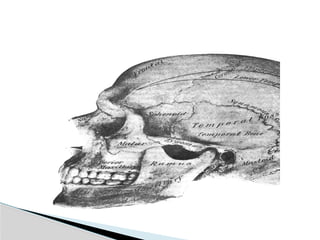

Mandible Anatomy

Classification (Lindhal, 1977) A) Fracture level 1) Condylar head( ) 2) condylar neck 3) subcondylar (high or low)

 B) Relationof condyle to mandible 1) Non displaced 2) Diviated angulated 3) Displaced ( M or L/A or P overlap)  C) Relation of condyle to glenoid fossa 1) Non dispalced 2) Displaced-still related to fossa 3) Dislocation-completely out of fossa (head usually anteriomedial)